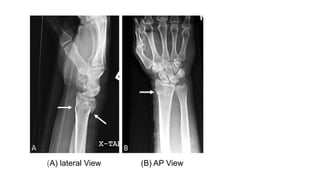

Colles Fracture

Colles’ fracture specifically is defined as metaphyseal injury of cortico-cancellous junction (within 2−3

cm of articular surface) of the distal radius with characteristic dorsal tilt, dorsal shift, radial tilt, radial

shift, supination and impaction.

These distal radius fractures are often caused by falling on an outstretched hand with the wrist in dorsiflexion,

causing tension on the volar aspect of the wrist, causing the fracture to extend dorsally.

On X-Ray, the wrist will present with what is known as the “dinner-fork” deformity.

(A) lateral View (B) AP View